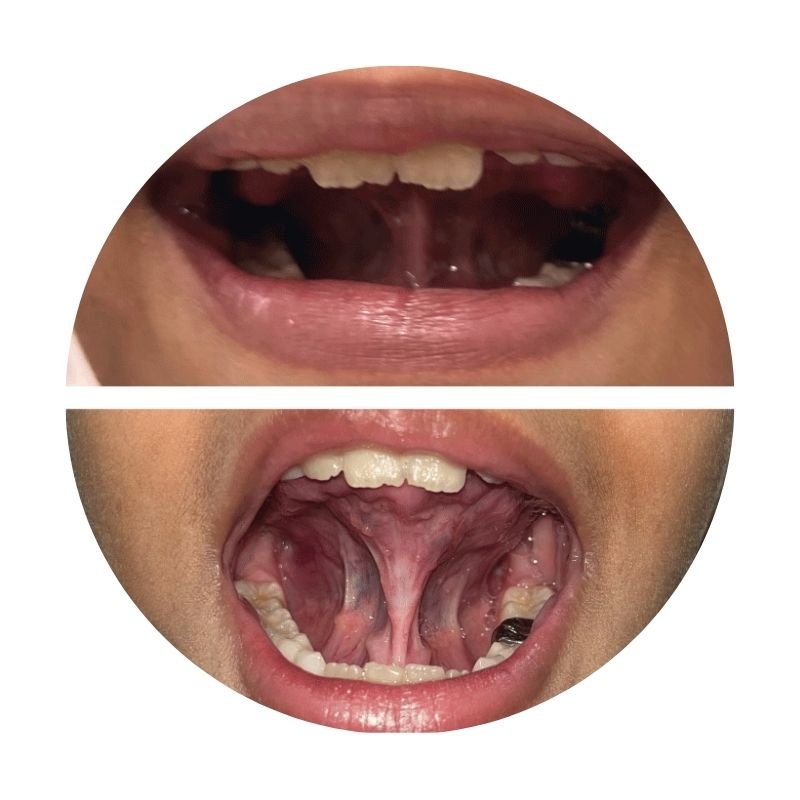

Lasers for tongue tie correction: improves speech, jaw development

Laser

A tongue tie is a short, tight band under the tongue that restricts normal movement. Usually present from birth, it can cause difficulties with breastfeeding, eating, or speech.

Dr. Anushree Khatri specialises in laser-assisted tongue-tie release, performed in a single visit with minimal bleeding, quick healing and no stitches.

The procedure helps with smooth feeding in newborns, supporting healthy growth, and also resolves breastfeeding challenges for new moms. In older children, it improves speech and oral function.